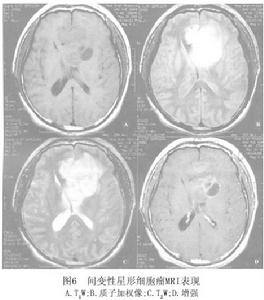

間變性星形細胞瘤在MRI上,腫瘤T1W為低信號 T2W為高信號,較多形性膠母細胞瘤影像稍均勻, 無壞死或出血灶。增強後,80%~90%腫瘤有強化(圖6)。腫瘤強化表現不一,可為環形 結節形、不規則形等,另有部分腫瘤強化均勻一致。